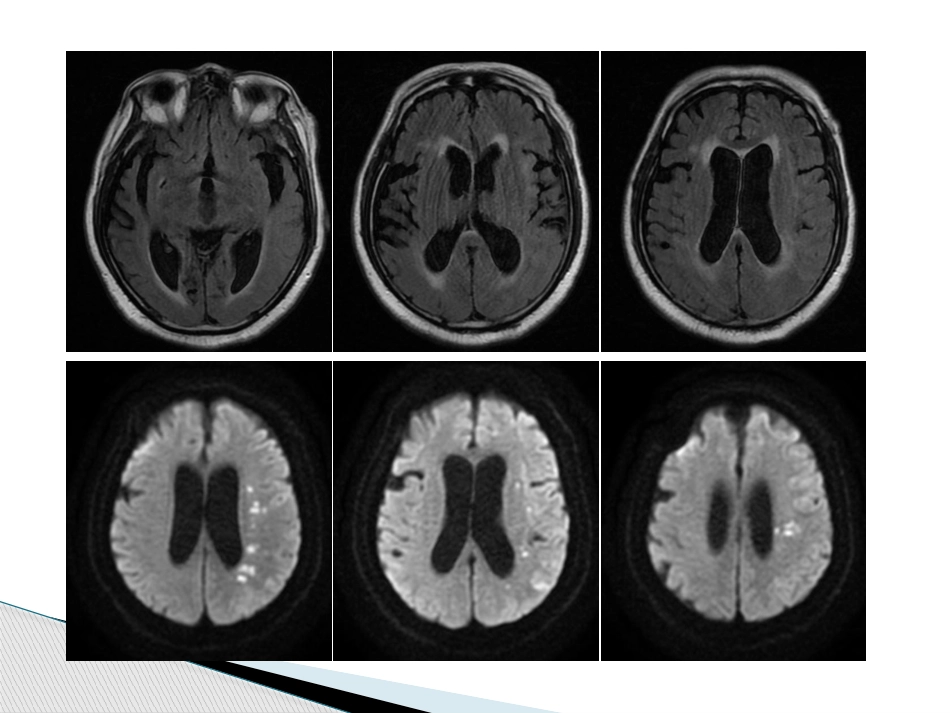

教学查房2019-01-09神经内科病史回顾患者,男,69岁,已婚。因“反应迟钝3月,加重1周”于2018-12-29入院。既往有“高血压病、垂体瘤、脑梗死、前列腺增生”史。查体:BP:132/62mmHg,神志清,精神萎,反应迟钝,两侧瞳孔等大等圆,直径2.5mm,光反应灵敏,口齿不清,右侧鼻唇沟浅,伸舌偏右,颈无抵抗,两肺呼吸音粗,未闻及干湿啰音。心率82次/分,律齐,未闻及杂音。腹平软,无压痛,肝脾肋下未及。右侧肢体肌力3级,左侧肢体肌力4级,肌张力正常,感觉及共济运动检查不合作,双侧Babinskisign阴性。辅助检查:TPHA(2018-12-27,本院)阳性,RPR阳性+;RPR滴度(2018-12-28,本院):RPR(1:2)阳性+,RPR(1:4)弱阳性+。头颅MRI+MRA(2018-12-25,本院):左侧放射冠区、半卵圆中心及左颞枕顶叶多发散在点片状急性脑梗塞,脑干、两侧基底节、放射冠区多发腔隙性脑梗塞,白质脱髓鞘改变,脑萎缩,鞍区占位性病变,考虑垂体瘤,提示颅内动脉粥样硬化,左侧大脑中动脉分支稀疏。脑脊液免疫检验报告:TPHA阳性+,RPR阳性+,RPR(1:2)弱阳性±。神经梅毒neurosyphilis锡山人民医院神经内科猜一猜那些名人们?法国文学家福楼拜,一生未婚,从年少时期开始,他便时常出入妓院。他后来坦承,他或许在二十岁进巴黎法学院之前就已染上了梅毒。福楼拜临终时也出现了梅毒精神病症状,他的学生莫泊桑写道:“这是好死,令人羡慕的大棒一击,这使我也希望这样,也希望我所爱的人都这样,像被一只巨大的手指掐死一只昆虫那样死去。”包法利夫人猜一猜那些名人们?莫泊桑作为福楼拜的学生,他继承了老师放荡的衣钵。莫泊桑一生有三大喜好——写作、游艇、美女——他酷爱女色,热衷于和包括饭馆侍女、农庄姑娘、寡妇、黑人女性、成熟女市民在内的女人鬼混,妓院更是他流连忘返的地方。最终,醉生梦死的纵欲生活,让他染上了梅毒。他的人生最后18个月,是在疯人院里度过的。漂亮朋友猜一猜那些名人们?贝多芬终生没有结婚,但是在他成名后贝多芬有了花不完的金钱和女性崇拜者,他一方面不停地去妓院,另外一方面也不断的和自己的崇拜者发生关系。1797年贝多芬就出现了梅毒引起的耳聋症状,经过长时间治疗没有效果,一直到最后贝多芬彻底丧失了听力。1827年3月26日,贝多芬因为梅毒而死亡。猜一猜那些名人们?1888年,梵高来到了法国南部的小城阿尔,在这里他与画家高更共用一个叫做拉舍尔的妓女。最后发生了著名的“割耳事件”,梵高割下来自己的耳朵,把它送给了妓女拉舍尔。这个事件让梵高难以见容于当地居民,梵高被迫离开阿尔,前往圣雷米的精神病院接受治疗,最终在1890年7月27日在圣雷米的一个小河边开枪自杀。猜一猜那些名人们?天朝的民间音乐家阿炳也是一个梅毒患者。阿炳是道观的一个乐师和一个富家小姐的私生子,他出生后跟着父亲在道观长大,长大后也成为一名乐师。他年轻时嫖妓不慎染上了梅毒,眼睛瞎了以后不能继续在道观当乐师,于是沦落到街头卖艺。《二泉映月》等传世名曲就是那时候谱成的。视力损害、听力损害头晕、头痛、呕吐、眩晕癫痫发作、偏瘫、失语、感觉障碍、意识障碍眼肌麻痹、瞻望、痴呆脊髓损害症状、截瘫、尿便障碍、性功能障碍发病可急可慢症状(symptom)症状(symptom)变化多端梅毒(syphilis)1.梅毒螺旋体:生物病原体,苍白密螺旋体2.慢性传染性疾病,全身组织及系统,包括神经系统3.传播途径:性接触、破损皮肤及粘膜(血液)4.具体路径:血循环-螺旋体血症;伤口-淋巴管-组织器官及血循环-螺旋体血症-各部位免疫反应5.机体应答:中和抗体(10-21天),不能限制增殖和发展;细胞免疫,可以限制增殖和发展。6.由于细胞免疫导致症状的不同:慢性;细胞免疫缺陷者病理改变:脑(脊)膜的炎症和小动脉的血管内膜炎。基本路径:梅毒血症—细胞免疫反应—反应的结果—完全治愈或疾病进展—产生脑动脉炎或局灶性侵犯神经阻织—产生没有症状或缓慢进展的神经症状—痴呆病理分型:脑膜血管型和脑实质型归纳总结脑膜炎:慢性脑膜炎(头痛、眩晕、呕吐、脑积水、认知障碍、颅内压增高、面、听、外展、动眼神经损伤等)...